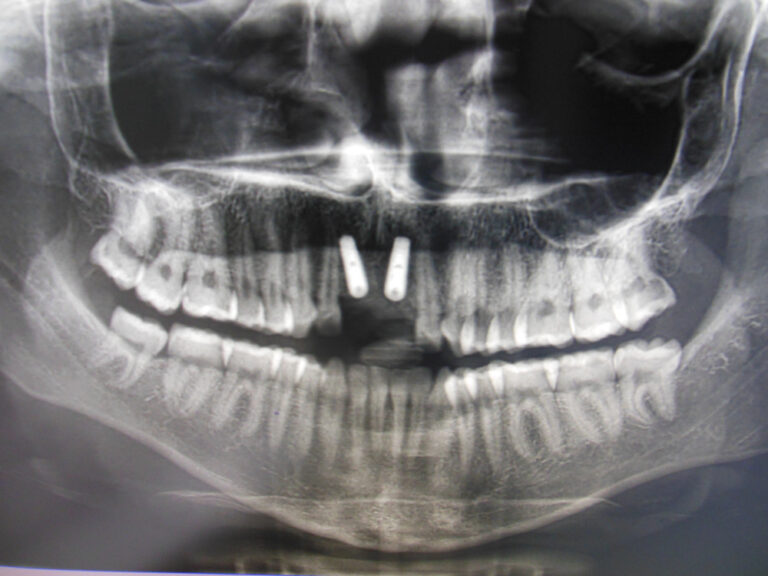

Przykłady implantologii

Zastosowanie implantoprotetyki w przypadku gdy klasyczna protetyka nie sprawdza się.